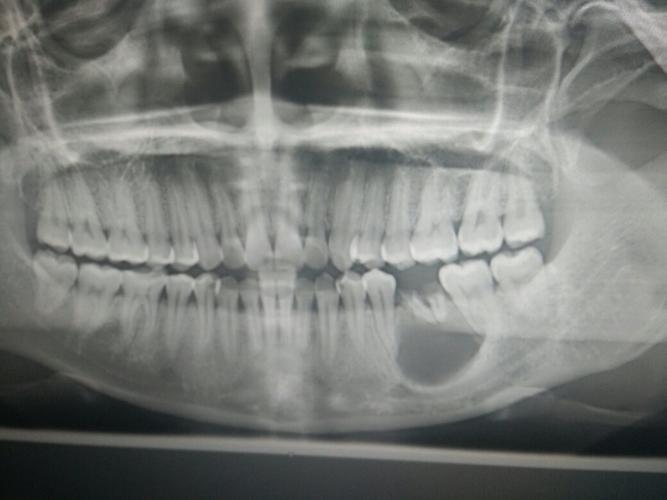

这位医生并没有想到,一次看似简单的牙根截根手术竟然会引发如此令人震惊的并发症。在手术过程中,医生小心翼翼地处理着牙根,试图将其顺利截断。就在医生以为一切都进行得很顺利的时候,牙根竟然发出了“咔嚓”的声音,折裂成了两半!医生当时的表情可想而知,惊讶得下巴都要掉到地上了。

那么,为什么那颗牙根会折裂呢?医生经过仔细的观察和分析后发现,这颗牙根的内部结构异常复杂,存在一些微小的裂纹。而在牙根截根手术过程中,由于受到了一定的力量,这些微小的裂纹逐渐扩大,最终导致了牙根的折裂。

牙根折裂的后果牙根折裂的后果可不容小觑。牙根折裂后,无法像正常情况下那样顺利进行截根手术,需要医生采取其他更复杂的治疗方式,比如拔牙。牙根折裂还可能导致周围组织的感染和疼痛,给患者带来不必要的痛苦和烦恼。